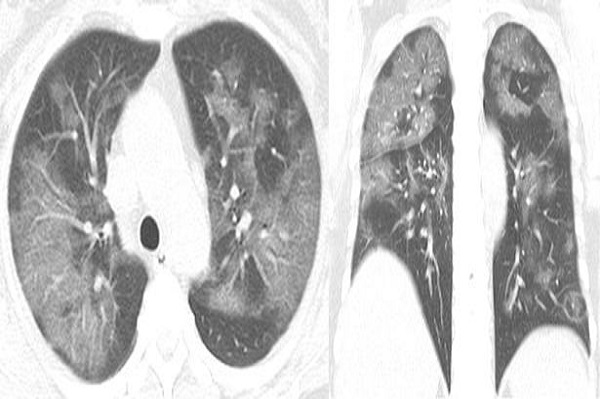

| Foto paru-paru wanita Inggris berusia 54 tahun yang terinfeksi COVID-19. Foto/RSNA |

Orang Inggris pertama yang terifeksi COVID-19 telah mengatakan bagaimana penyakit itu menimpanya seperti "kereta api" dan membuatnya seperti "mati lemas" serta kesakitan selama beberapa minggu. Dia adalah seorang wanita berusia 54 tahun yang dites positif terinfeksi virus corona baru setelah mengunjungi Wuhan, China. Hasil CT scan menunjukkan ada bercak putih di paru-parunya.

Kelainan seperti itu dikenal sebagai ground glass opacity atau cairan di ruang-ruang di paru-paru, dan kondisi itu menjadi lebih jelas ketika di-scan lebih lanjut. Wanita itu dirawat di rumah sakit setelah demam selama seminggu, sakit batuk, kelelahan dan dada seperti tersumbat.

Dia didiagnosis menderita pneumonia COVID-19 yang parah dan diobati dengan oksigen dan antibiotik.

Dalam kasus lain, seorang pria berusia 44 tahun yang bekerja di pasar makanan laut Wuhan, China, pergi ke rumah sakit setelah menderita demam tinggi dan batuk selama hampir dua minggu pada 25 Desember lalu tahun. CT scan dada menunjukkan bercak yang sama dan scan yang dilakukan lebih lanjut menunjukkan bagaimana kekeruhan pada paru-parunya menyebar.

Pria itu didiagnosis menderita pneumonia berat dan sindrom gangguan pernapasan akut, tetapi dia meninggal seminggu kemudian.